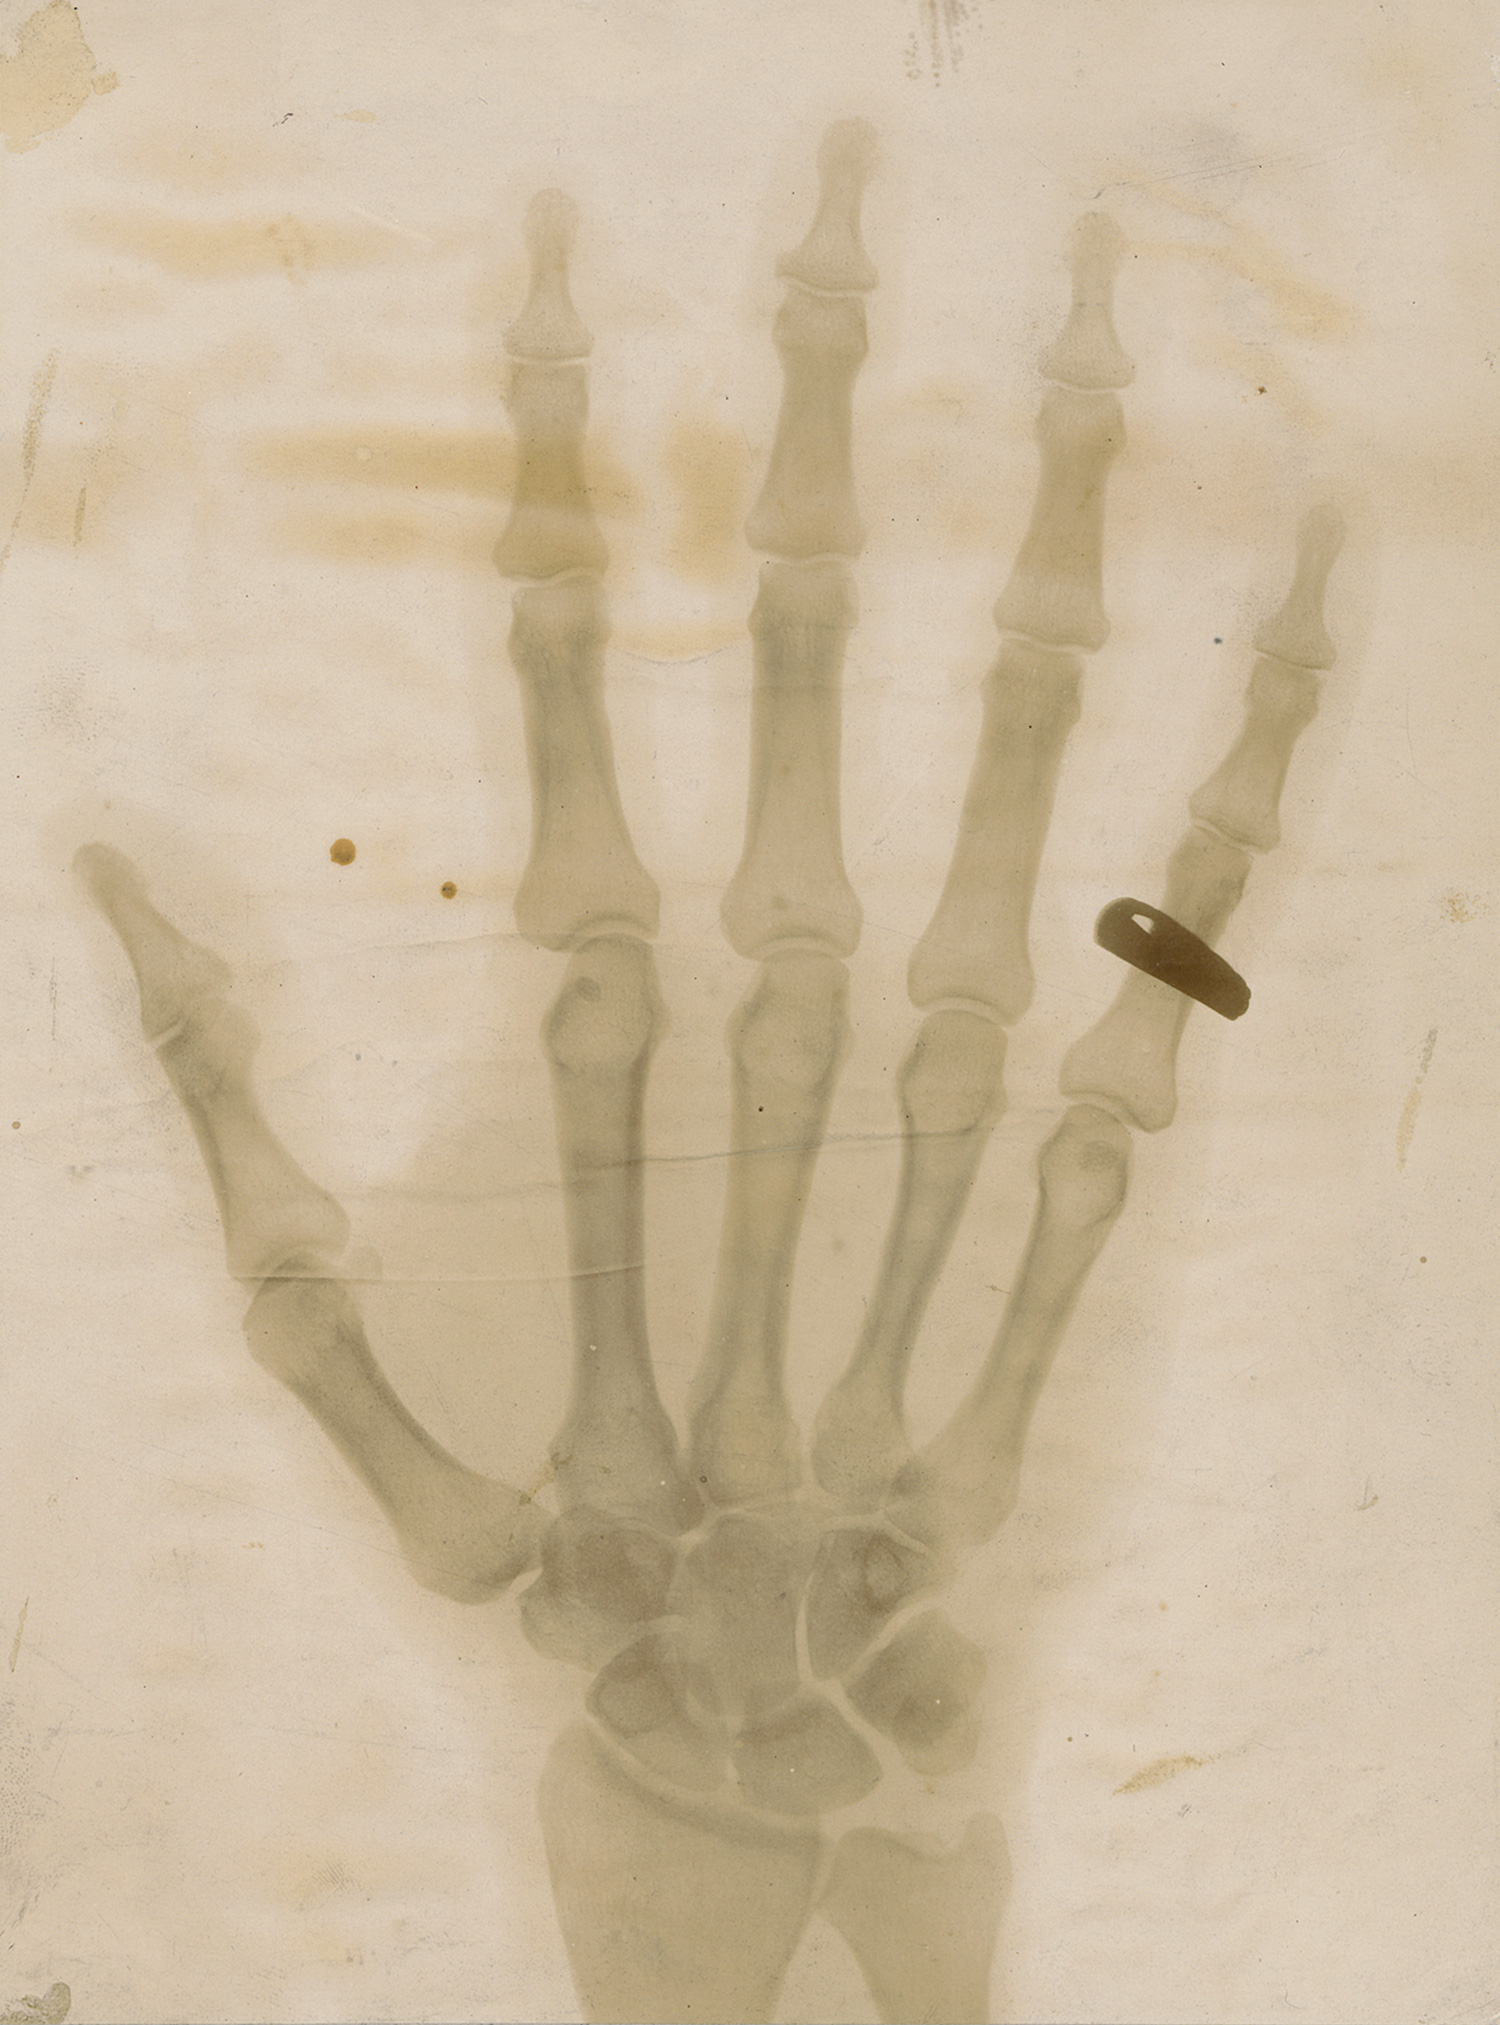

X-ray of a hand with a ring

Photographer unknown. X-ray of a hand with a ring. Circa 1910. Vintage collodion print. 22,5 x 17 cm. Mounted to original board with gilt-ruled outline.

This striking early radiographic image captures the skeletal structure of a hand adorned with a ring, exemplifying the fascination with X-ray technology following its discovery by Wilhelm Röntgen in 1895. Likely made for scientific or medical demonstration, the print highlights the translucency of flesh and the opacity of metal in dramatic contrast. – Buckling from mounting, a few small spots and areas of discoloration, liquid staining in upper and lower corners, slightly faded.